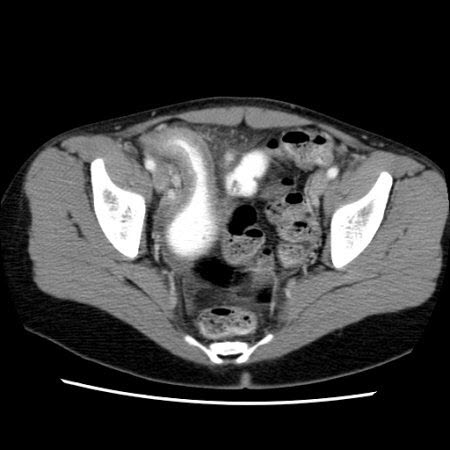

Doença de Crohn: Tomografia computadorizada (TC) mostrando espessamento do íleo terminal em um paciente com exacerbação da doença de Crohn

Fornecido pelo Dr. Wissam Bleibel, Dr. Bishal Mainali, Dr. Chandrashekhar Thukral e Dr. Mark A. Peppercorn